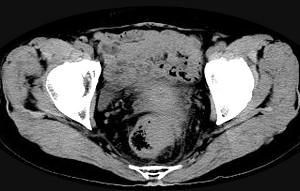

问题 男,56岁,排便形状改变,便不尽感,CT检查如图所示,下列说法正确的是 ( )

选项 A、此为直肠息肉 B、此为直肠癌 C、其表面光滑,边界清楚 D、肠腔未见狭窄 E、肠壁上有蒂状新生物

答案 B